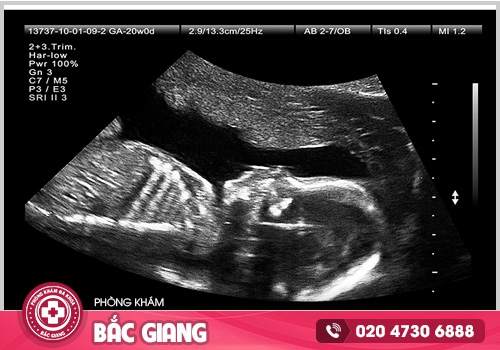

BÁC SĨ SẼ ĐÁNH GIÁ GÌ KHI SIÊU ÂM THAI?

Trong quá trình siêu âm thai, đặc biệt là lần siêu âm đầu tiên, bác sĩ sẽ tiến hành kiểm tra và đánh giá một số yếu tố quan trọng liên quan đến sức khỏe của mẹ và thai nhi.

Xác định tuổi thai: Bác sĩ sẽ đo kích thước của thai nhi để xác định tuổi thai. Việc này giúp xác định liệu thai nhi phát triển đúng tuần thai hay không.

Kiểm tra vị trí thai nằm trong hay ngoài tử cung: Bác sĩ sẽ đo kích thước và kiểm tra vị trí của tử cung để đảm bảo thai nhi phát triển trong tử cung một cách bình thường. Loại trừ trường hợp thai ngoài tử cung, cần có biện pháp can thiệp sớm.

Kiểm tra nhịp tim thai: Bác sĩ sẽ lắng nghe và ghi nhận nhịp tim của thai nhi. Điều này rất quan trọng để đảm bảo sự phát triển và sức khỏe của thai nhi.

Đánh giá lượng nước ối: Bác sĩ sẽ đánh giá lượng nước ối có trong tử cung để xem liệu thai nhi đang phát triển bình thường hay có dấu hiệu bất thường.